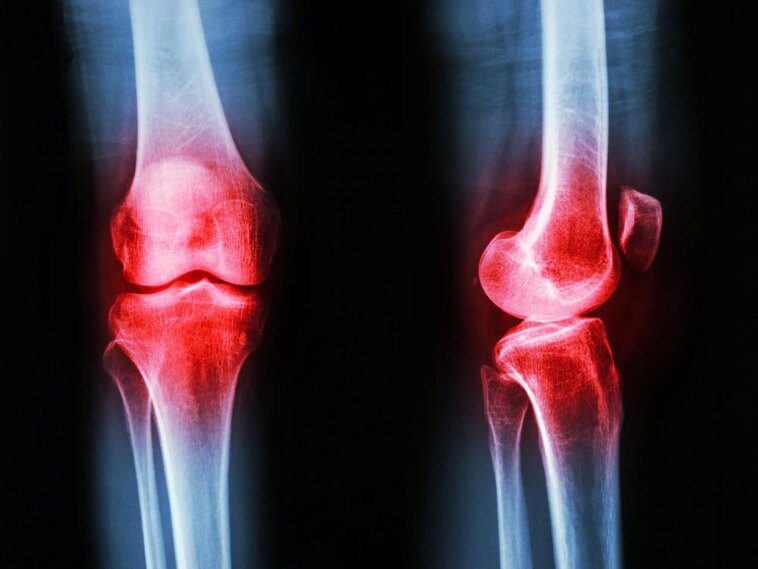

Osteoarthritis Knee Inflammation

L’arthrose implique la dégradation du cartilage et des tissus articulaires environnants et constitue la forme d’arthrite la plus courante en Australie, avec 20 % des personnes de plus de 45 ans qui en souffrent.